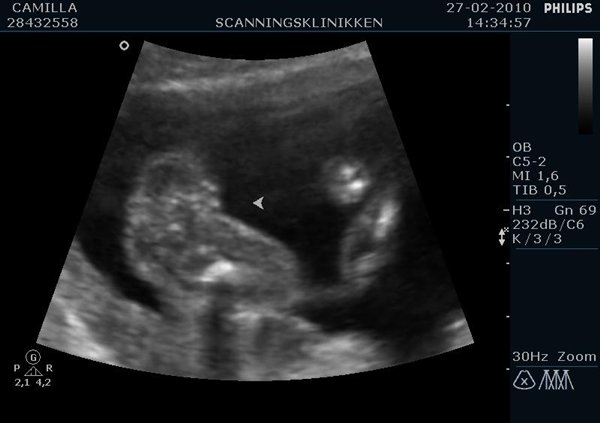

Ville lige ligge lidt billeder ind af min lille pige (Emilie?)  fra kønsscanningen igår

Vedhæftede fotos (klik for at se i fuld størrelse)

Billedet af hendes ædlere dele beviser 2stk skamlæber, (de to prikker)

Jordemoderen scannede mig fra alle leder og kanter og der var hverken tap eller pung at finde